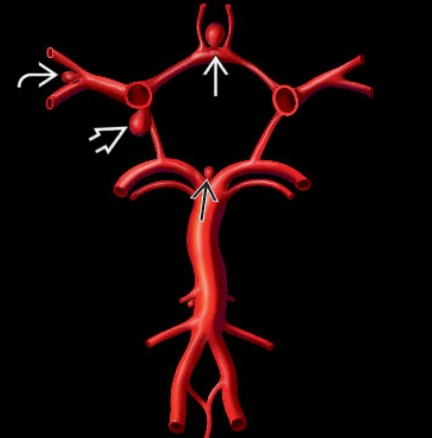

• Phình mạch não dạng túi (Saccular cerebral aneurysm)

• Phình mạch não do nhiễm trùng (Intracranial Mycotic Aneurysm / Intracranial Infectious Aneurysm)